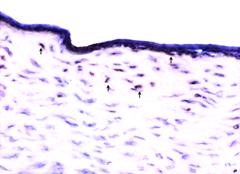

α-SMA在正常角膜组织几乎不表达。术后7天,α-SMA阳性细胞在Epi-LASIK与LASEK术后的上皮下的浅层基质中开始明显出现,在术后1月均达到最高峰,LASEK较Epi-LASIK组增强更明显(见图4、5)。术后3月,Epi-LASIK与LASEK的平均α-SMA阳性基质细胞数分别为2.1±0.74和4.8±1.03,两者差异有统计学意义(P<0.01)。Epi-LASIK与LASEK术后1周、1月和3月每个高倍镜下的平均α-SMA阳性基质细胞数与对照组相比差异均有统计学意义(P<0.01)。Western bolt法对α-SMA定量结果示:LASEK与Epi-LASIK术后1周、1月和3月的α-SMA蛋白表达与对照组相比有统计学意义,且组间差异有统计学意义(P<0.01)。

图4 Epi-LASIK术后1m角膜α-SMA染色